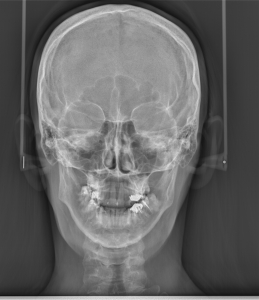

Телерентгенография – лицева проекция фас

Телерентгенография в лицева проекция дава възможност да се диагностицират изменения, фрактури, възпалителни и неопластични заболявания на костните структури на черепа и лицевите кости.

Рентгеноват снимка на черепа в лицева проекция се използва за диагностициране на фрактури на черепните и лицевите кости. Чрез тази рентгенова снимка могат да се установят вродени аномалии, тумор на хипофизата, както някои метаболитни, ендокринни и възпалителни заболяванияа  водещи до промени в костите на черепа.